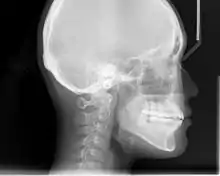

In the postwar period, cephalometric radiography[12] started to be used by orthodontists for measuring changes in tooth and jaw position caused by growth and treatment.[13] The x-rays showed that many Class II and III malocclusions were due to improper jaw relations as opposed to misaligned teeth. It became evident that orthodontic therapy could adjust mandibular development, leading to the formation of functional jaw orthopedics in Europe and extraoral force measures in the US. These days, both functional appliances and extraoral devices are applied around the globe with the aim of amending growth patterns and forms. Consequently, pursuing true, or at least improved, jaw relationships had become the main objective of treatment by the mid-20th century.[6]

An X-ray taken for skull analysis